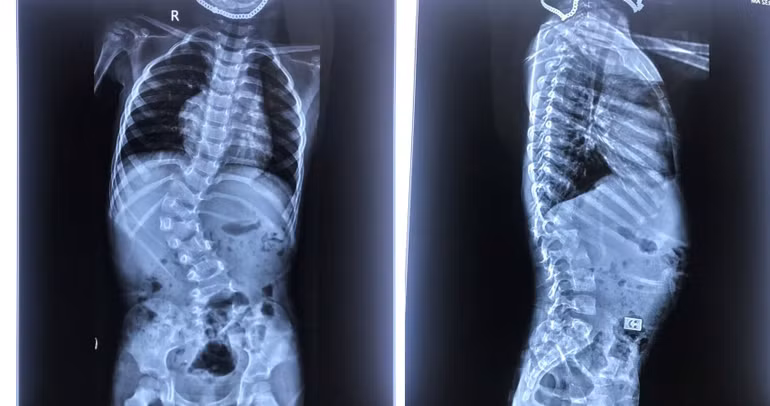

Bốn năm trước, bệnh nhi B.Đ (3 tuổi, Thanh Hóa) được phẫu thuật nắn chỉnh biến dạng cột sống tại Bệnh viện Trung ương Quân đội 108. Bệnh nhi bị vẹo cột sống ngực-thắt lưng bẩm sinh mức độ lớn do dị tật nửa đốt sống L1 từ 2 tuổi, dẫn đến cúi ngửa khó khăn, hạn chế vận động.

Tình trạng biến dạng cột sống của cháu B.Đ đã là mức độ nặng, góc vẹo 66 độ, nếu trì hoãn mổ đợi khi cháu được 6 tuổi trở lên thì không thể phẫu thuật nắn chỉnh được vẹo cột sống. Các bác sĩ quyết định phẫu thuật can thiệp, mang lại cuộc đời mới cho bệnh nhi.

Sau mổ, bệnh nhi đã được nắn chỉnh tốt biến dạng cong vẹo cột sống, không có tổn thương thần kinh. Bệnh nhi hồi phục thuận lợi, hai chân vận động bình thường và đã có cuộc sống mới 4 năm qua.

| Hình ảnh X-quang trẻ cong vẹo cột sống. |